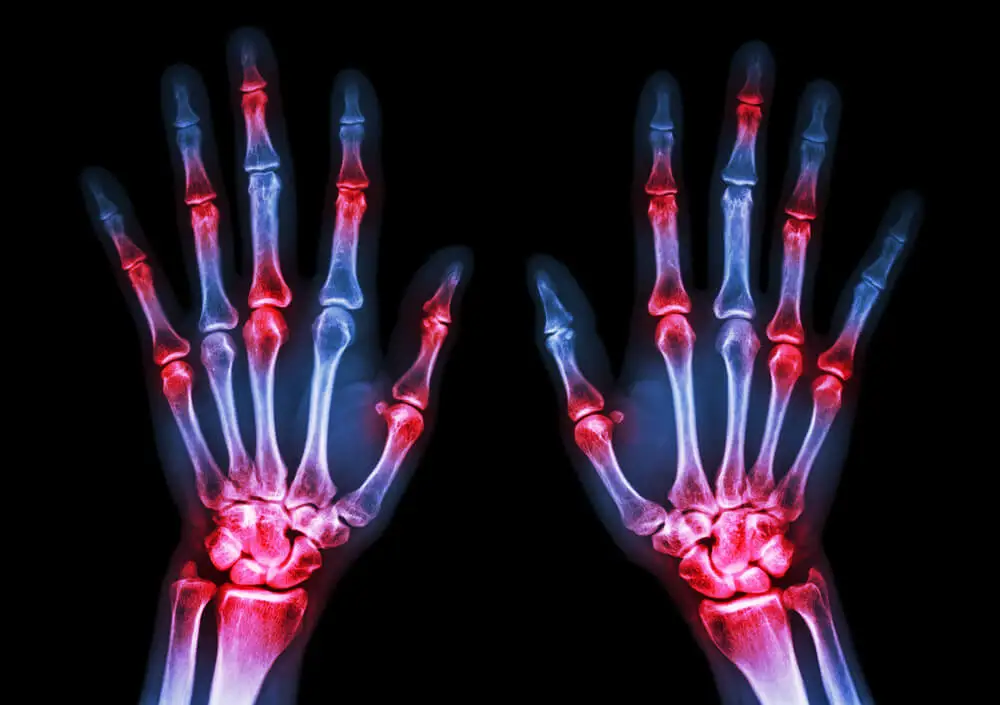

- El grado de maduración ósea debe evidenciar un retraso. Para ello, se realizan estudios complementarios de imágenes que permiten medir la densidad de los huesos y su conformación interna.

Por un lado, existe la posibilidad de que se retrase la pubertad. Esto afecta el desarrollo de los huesos y hace que los pacientes sean más propensos a las fracturas y lesiones.